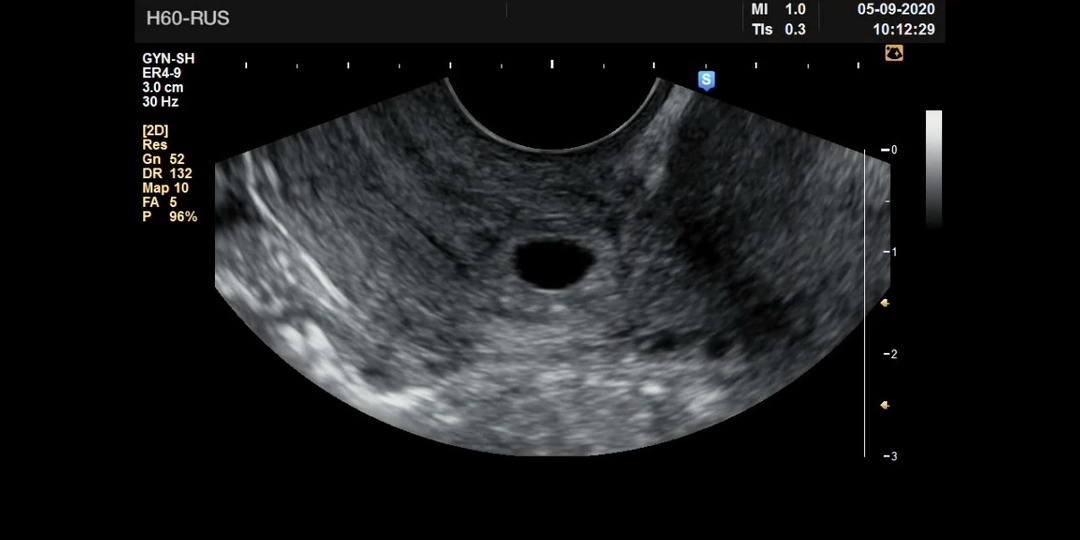

У Инны это была уже четвертая беременность. Первому ребенку недавно исполнилось 7.  Затем две неудачные беременности. При второй на скрининге в 20 недель обнаружили гастрошизис. Решили прерывать.  Гастрошизис – аномалия развития, при которой в результате раннего нарушения развития  органы брюшной полости из-за врожденного дефекта передней брюшной стенки  развиваются вне туловища эмбриона, что влечёт за собой не только неправильное развитие этих органов, но и дефекты формирования как брюшной полости, так и грудной клетки. Третья - биохимическая, в матке так и не появилась.  Лечащий доктор заботливо назначил дидрогестерон, видимо, посчитав, что эти две «неудачи» равно «привычный выкидыш». Хотя, конечно, порок развития плода к дефициту прогестерона отношения не имеет.  Через год после  третьей — наконец снова две полоски.  Инна очень боялась повторения биохимической беременности, и сразу пошла сдавать анализ на ХГЧ.  И в этот же день пришла ко мне на УЗИ.  Задержка буквально пару дней